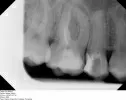

Во время отдыха у меня началось сильное воспаление над пятым и шестым зубами верхней челюсти. В шестом стоит старая пломба. Дантист поставил диагноз, который звучит как «16 симптоматический верхушечный периодонтит с щечным свищом».

Насколько это серьезно? Мне кажется, или в шестом зубе действительно есть перфорация к верхушке корня? Как это лечить, чтобы сохранить зуб? Врач отказался очищать каналы от старой пломбы под предлогом, что один из трех каналов слишком узкий и кривой, и послал меня к эндодонтисту. А его долго ждать надо. Нужно ли пить антибиотики? Посылаю рентген, чтобы Вы могли оценить ситуацию.

На этом снимке ничего не видно и поставить однозначный диагноз, вернее решить судьбу зуба невозможно. Шансов на полное выздоровление данного зуба очень мало, но попробовать пролечить стоит, если, конечно, нет перфорации. В гос. поликлинике это воспаление Вам никогда не вылечат, поэтому обратитесь к опытному специалисту.